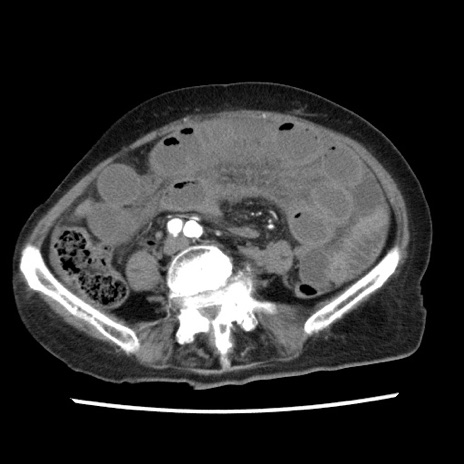

症例1(横断像)

【症例】80歳代女性

【主訴】腹痛

【現病歴】8時間前から腹痛あり来院。

【既往歴】糖尿病、脂質異常症、子宮体癌にて子宮全摘術

【身体所見】意識清明・会話良好だが腹痛で苦悶様、全腹部にわたって反跳痛と圧痛あり

【データ】WBC 13600、CRP 0.14、LDH 224、CK 90